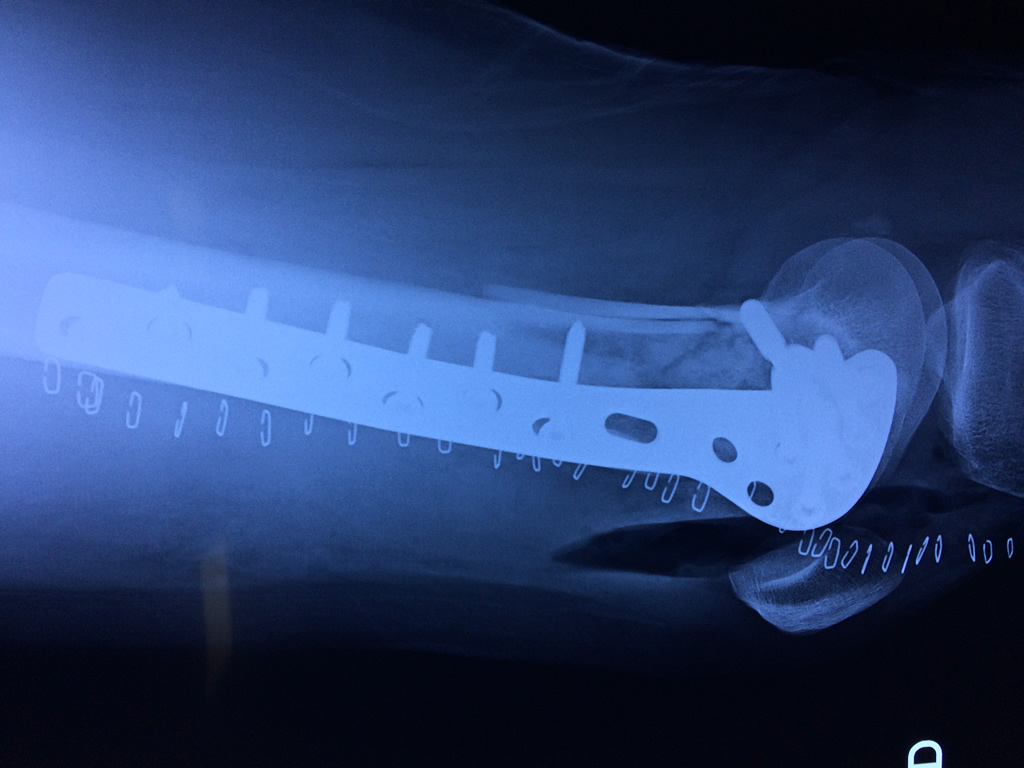

Cirugías de Cadera

El fémur es el hueso del muslo, el segundo segmento del miembro inferior. Es el hueso más largo, fuerte y voluminoso del cuerpo humano.